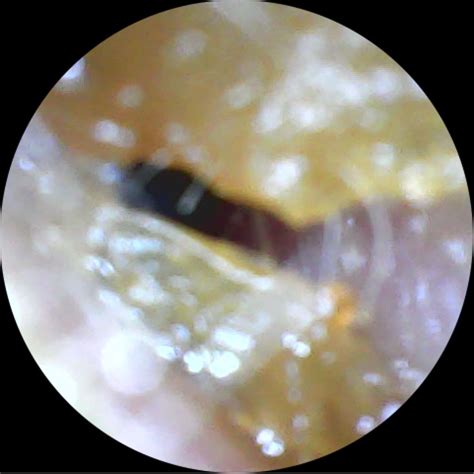

Earwax, also known as cerumen, is a natural substance produced by the body to protect the ear canal. However, when it becomes impacted or turns a reddish wax in ears, it can cause discomfort and even hearing loss. Understanding the causes, symptoms, and treatments for reddish wax in ears is crucial for maintaining ear health.

Diagnosing the cause of reddish wax in ears typically involves a physical examination by a healthcare professional. The doctor will use an otoscope to examine the ear canal and eardrum. Additional tests may be recommended based on the initial findings. These tests can include: